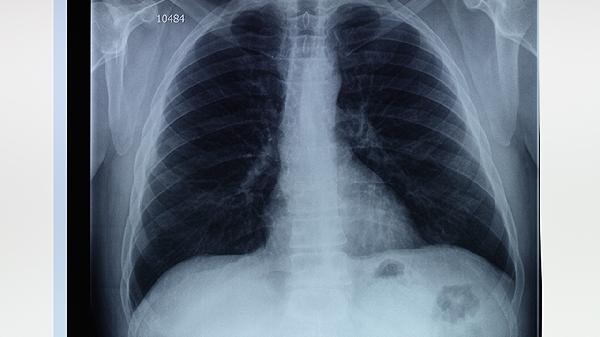

肺大泡是肺泡壁破裂后形成的异常气囊,多见于慢性阻塞性肺疾病COPD或肺气肿患者。虽然肺大泡本身并非癌性病变,但其存在可能提示肺部组织长期受损,增加了肺癌的发病风险。尤其是吸烟者,烟草中的有害物质会进一步损伤肺组织,导致细胞突变,最终可能发展为肺癌。

肺大泡的治疗目标是缓解症状、防止并发症并改善肺功能。戒烟是首要措施,可以显著降低肺癌风险。药物治疗包括使用支气管扩张剂和吸入性糖皮质激素,以减轻气道炎症和改善呼吸功能。对于较大的肺大泡或反复发生气胸的患者,可能需要手术干预,如肺大泡切除术或胸腔镜手术,以减少肺组织的进一步损伤。

除了治疗肺大泡,预防肺癌同样重要。定期进行低剂量胸部CT筛查,有助于早期发现肺癌病变。改善生活方式,如避免二手烟暴露、减少空气污染接触、保持健康饮食和适度运动,也能降低肺癌风险。对于有家族肺癌史或长期吸烟者,建议咨询医生制定个性化的筛查和预防计划。